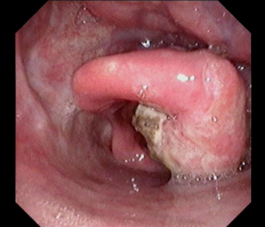

下咽癌颈淋巴结转移

下咽部淋巴组织丰富,较易发生淋巴结转移,早期常转移至同侧颈动脉三角区颈深部淋巴结,多为分化程度较差的癌。而且由于下咽部位置隐蔽,常常原发灶不易发现,还有转移灶很大,原发灶很小的情况。